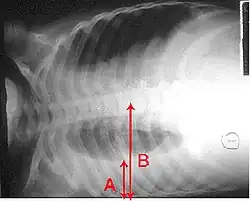

Anteroposterior chest X-ray of a pleural effusion. The A arrow shows fluid layering in the right pleural cavity. The B arrow shows the normal width of the lung in the cavity.

A large left-sided pleural effusion as seen on an upright chest X-ray

A pleural effusion is usually diagnosed on the basis of medical history and physical exam, and confirmed by a chest X-ray. Once accumulated fluid is more than 500 mL, there are usually detectable clinical signs, such as decreased movement of the chest on the affected side, dullness to percussion over the fluid, diminished breath sounds on the affected side, decreased vocal resonance and fremitus (though this is an inconsistent and unreliable sign), and pleural friction rub. Above the effusion, where the lung is compressed, there may be bronchial breathing sounds and egophony. A large effusion there may cause tracheal deviation away from the effusion. A systematic review (2009) published as part of the Rational Clinical Examination Series in the Journal of the American Medical Association showed that dullness to conventional percussion was most accurate for diagnosing pleural effusion (summary positive likelihood ratio, 8.7; 95% confidence interval, 2.2–33.8), while the absence of reduced tactile vocal fremitus made pleural effusion less likely (negative likelihood ratio, 0.21; 95% confidence interval, 0.12–0.37).[13]

Imaging

A pleural effusion appears as an area of whiteness on a standard posteroanterior chest X-ray.[14] Normally, the space between the visceral pleura and the parietal pleura cannot be seen. A pleural effusion infiltrates the space between these layers. Because the pleural effusion has a density similar to water, it can be seen on radiographs. Since the effusion has greater density than the rest of the lung, it gravitates towards the lower portions of the pleural cavity. The pleural effusion behaves according to basic fluid dynamics, conforming to the shape of pleural space, which is determined by the lung and chest wall. If the pleural space contains both air and fluid, then an air-fluid level that is horizontal will be present, instead of conforming to the lung space.[15] Chest radiographs in the lateral decubitus position (with the patient lying on the side of the pleural effusion) are more sensitive and can detect as little as 50 mL of fluid. Between 250 and 600mL of fluid must be present before upright chest X-rays can detect a pleural effusion (e.g., blunted costophrenic angles).[16]